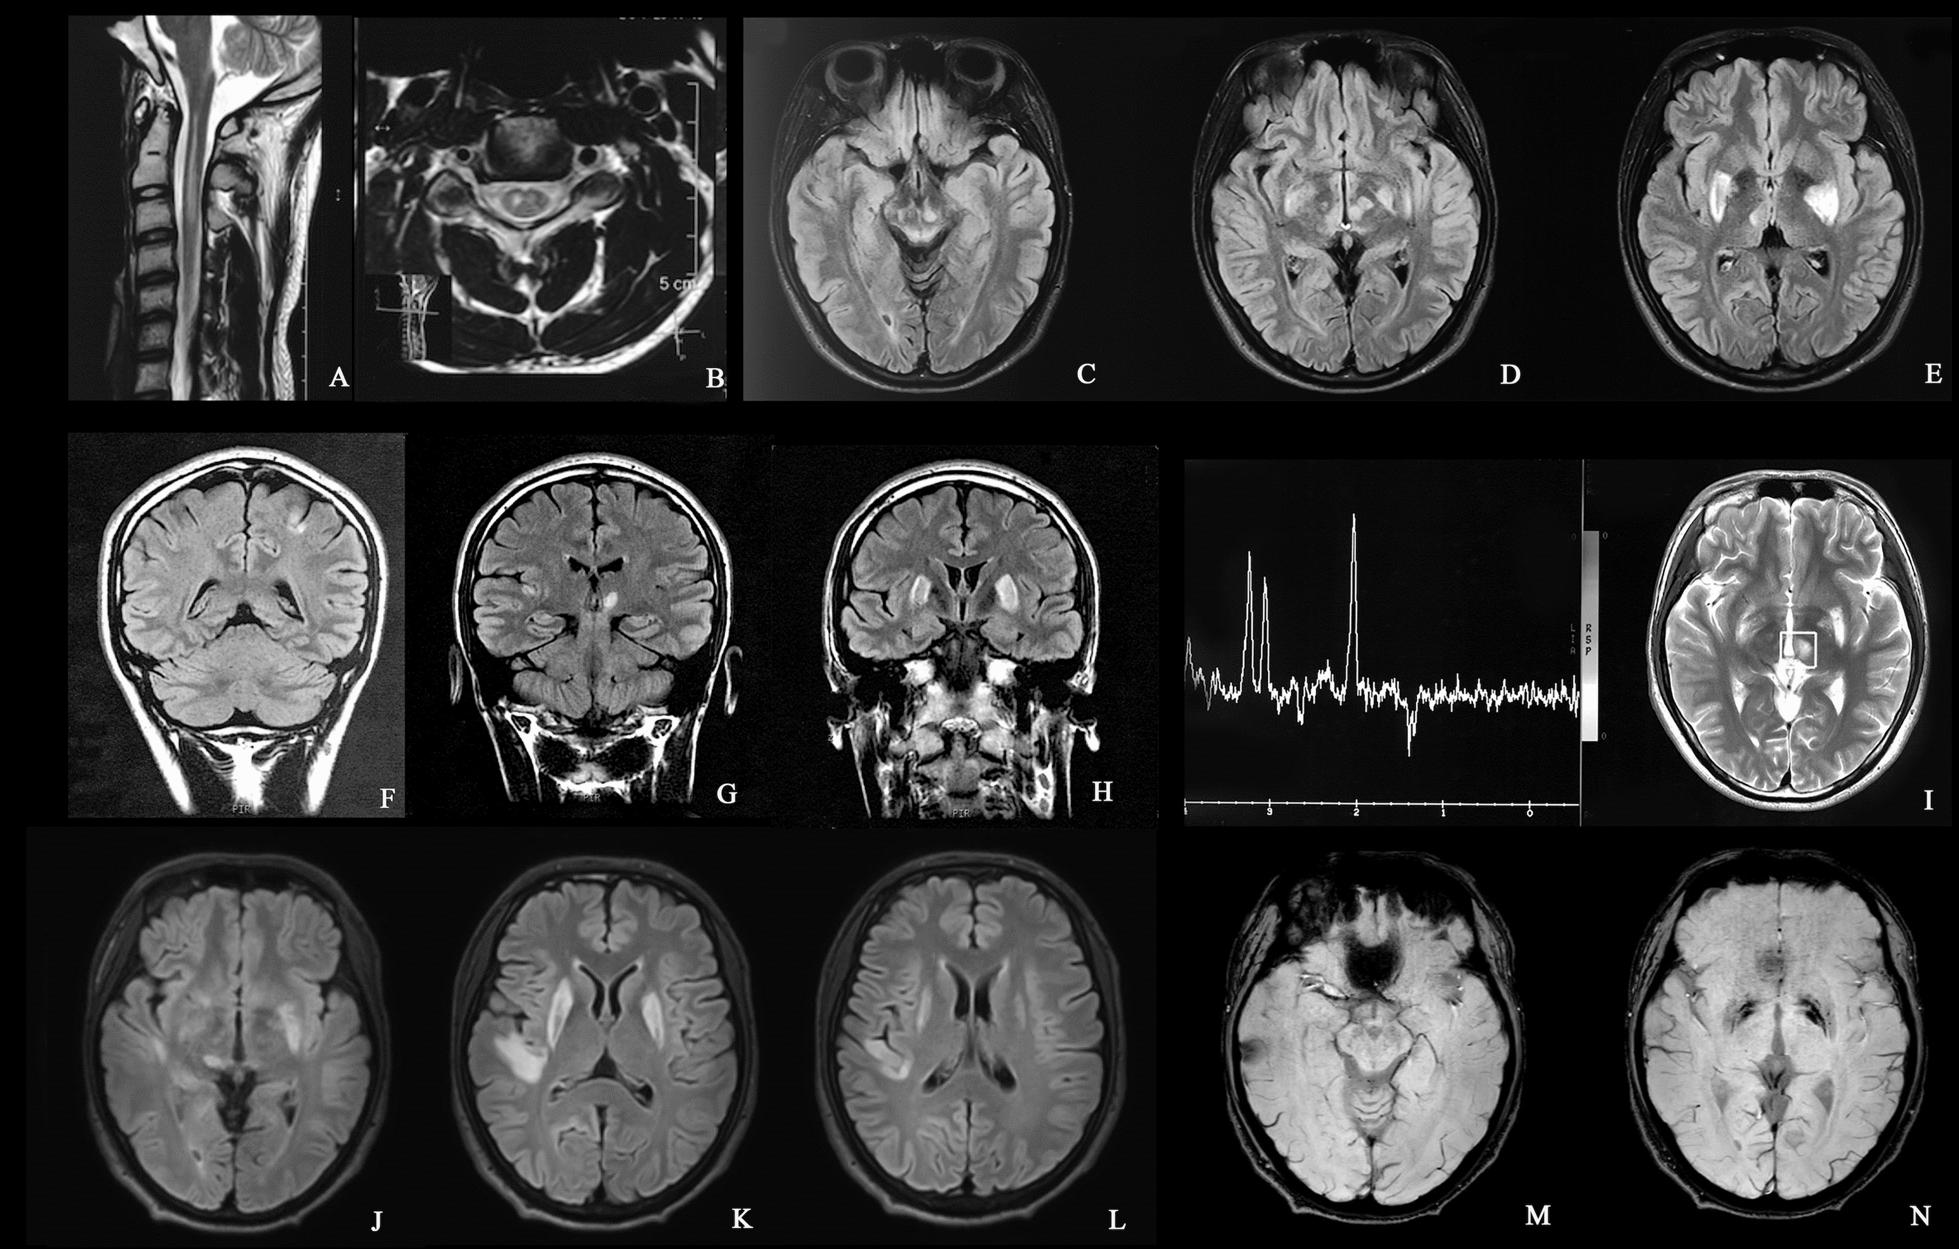

This study reports a rare case of adult-onset Leigh syndrome (LS) and Leber hereditary optic neuropathy and dystonia (LDYT) overlap syndrome caused by the m.10197G>A mutation in ND3. A review of the literature was conducted to investigate the clinical spectrum, treatment and outcome resulting from the m.10197G>A mutation. Phenotypes associated with the m.10197G>A mutation were classified into three categories: LS/LS+ (LS-involved overlap syndrome), Leber hereditary optic neuropathy (LHON)/LHON+ (LHON-involved overlap syndrome) and other mitochondrial encephalopathies or presentations.

本研究报告了一例由ND3基因m.10197G>A突变引起的成人起病的 Leigh 综合征(LS)与 Leber 遗传性视神经病变和肌张力障碍(LDYT)重叠综合征的罕见病例。通过文献回顾来研究m.10197G>A突变导致的临床谱、治疗及结局。与m.10197G>A突变相关的表型分为三类:LS/LS+(涉及LS的重叠综合征)、Leber遗传性视神经病变(LHON)/LHON+(涉及LHON的重叠综合征)以及其他线粒体脑病或表现。